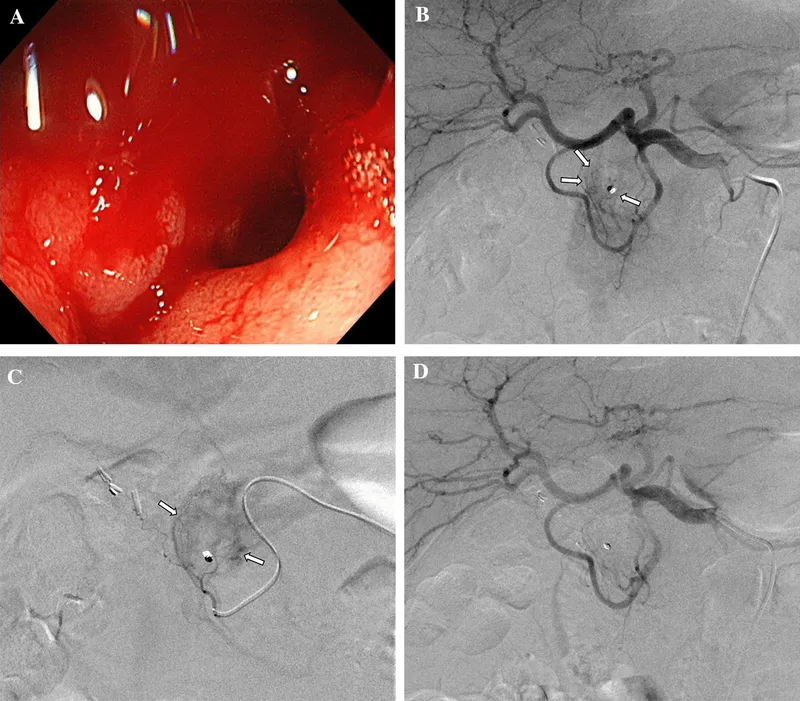

Embolization:

- Deliberate occlusion of a blood vessel to stop flow.

- Agents: Coils, particles, glue.

- Uses: Control active bleeding (trauma, GI bleed), treat tumors (chemoembolization), uterine fibroid embolization (UFE).

- Catheter-directed embolization is a primary treatment for acute hemorrhage, such as in GI bleeds or pelvic trauma.